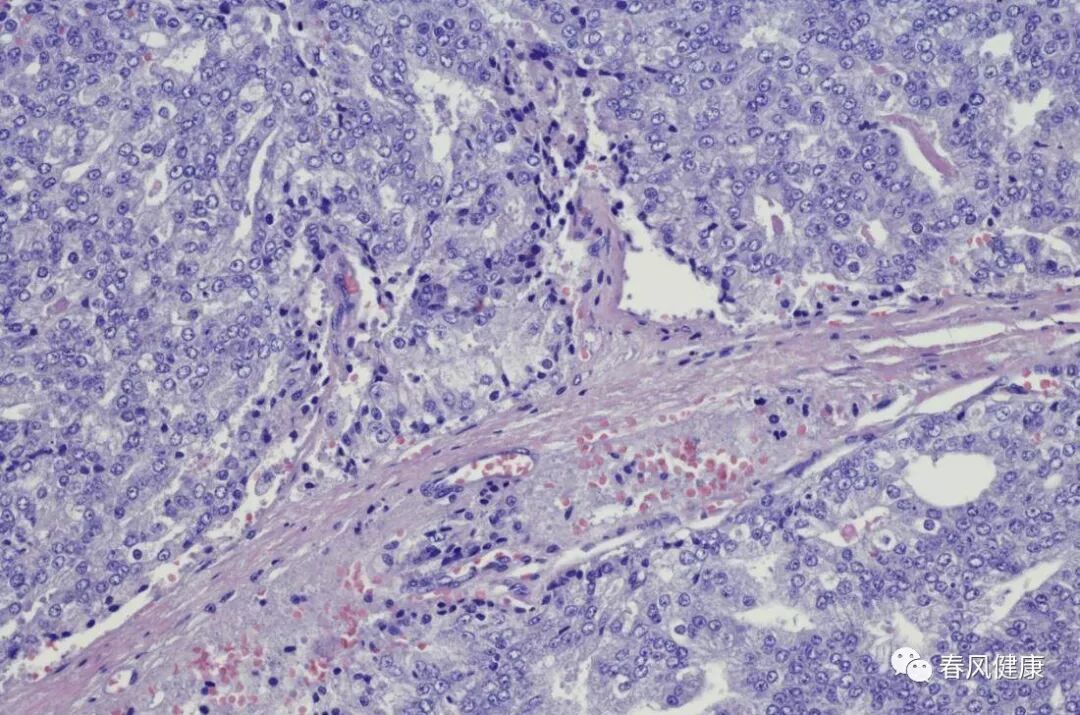

具体穿刺过程不再赘述,经过两天的等待,病理科报告穿刺结果:浸润性癌

穿刺枪怎么升级乳腺穿刺术(三)_https://www.jmylbn.com_新闻资讯_第4张

很多患者害怕空芯针穿刺会引起肿瘤扩散而拒绝行穿刺活检。这种担心是有道理还是多余的呢?

空心针穿刺的操作过程是每穿刺一次获得一小块组织,医生一般会反复进出肿块穿刺4~6次来取得足够量的标本,从而达到病理结果的准确全面客观。空芯针穿刺后是否会存在癌细胞的针道残留,是否会影响局部复发等安全性问题就备受患者和医生的关注。

国外有专家对1990~2008年共5369例行空芯针穿刺的乳腺癌患者进行汇总分析,发现针道肿瘤细胞的检出率为22%,但这并没有增加术后的局部复发率,随访结果证实空芯针穿刺和手术切除活检两组的局部复发率无明显差异。因为大多数患者空芯针穿刺不久就行全乳腺切除,就不存在针道肿瘤残留发生后遗症的问题。而对于有保乳意愿的患者,有经验的医生也会在行空芯针穿刺时,选择好合适的进针部位,以利于保乳手术时能将穿刺点和针道都包含在肿瘤局部广泛切除的范围之内,予以完整切除干净。